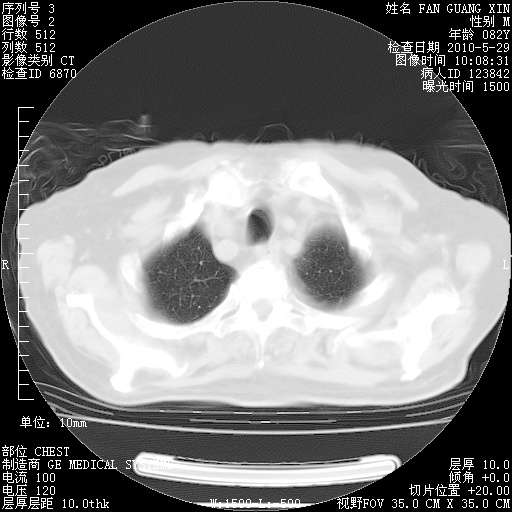

治疗3周后的肺部CT纵隔窗

再治疗10天后的肺部CT